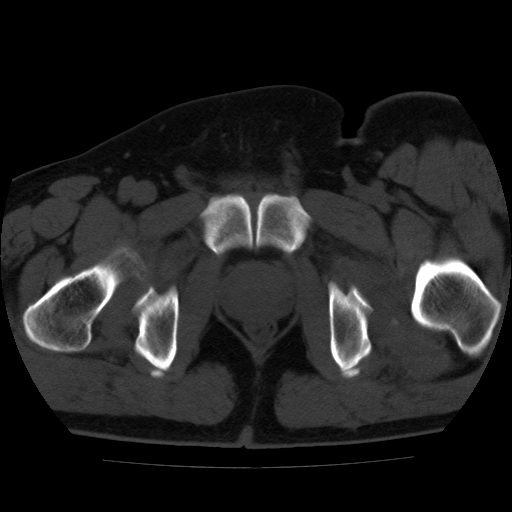

标题: CT21643:男,42岁,车祸伤后左髋关节疼痛剧烈1小时。 [打印本页]

男,42岁,车祸伤后左髋关节疼痛剧烈1小时。

左髋关节脱位并髋臼骨折,左髋关节积血。

左髋关节后脱位并髋臼骨折,左髋关节积血

左髋关节后脱位,大小转子皮质撕脱骨折,关节腔“脂血症”,左侧盆底少量积血,左侧髋臼邻关节囊肿。

左髋关节后脱位并髋臼骨折、股骨头前方骨折,左髋关节积血 。

左髋关节(股骨头)后脱位,并髋臼及股骨头骨折,左髋关节积血。

左髋关节后脱位并髋臼后缘骨折、股骨头前方骨折,左髋关节积血 。我遇到过一例。